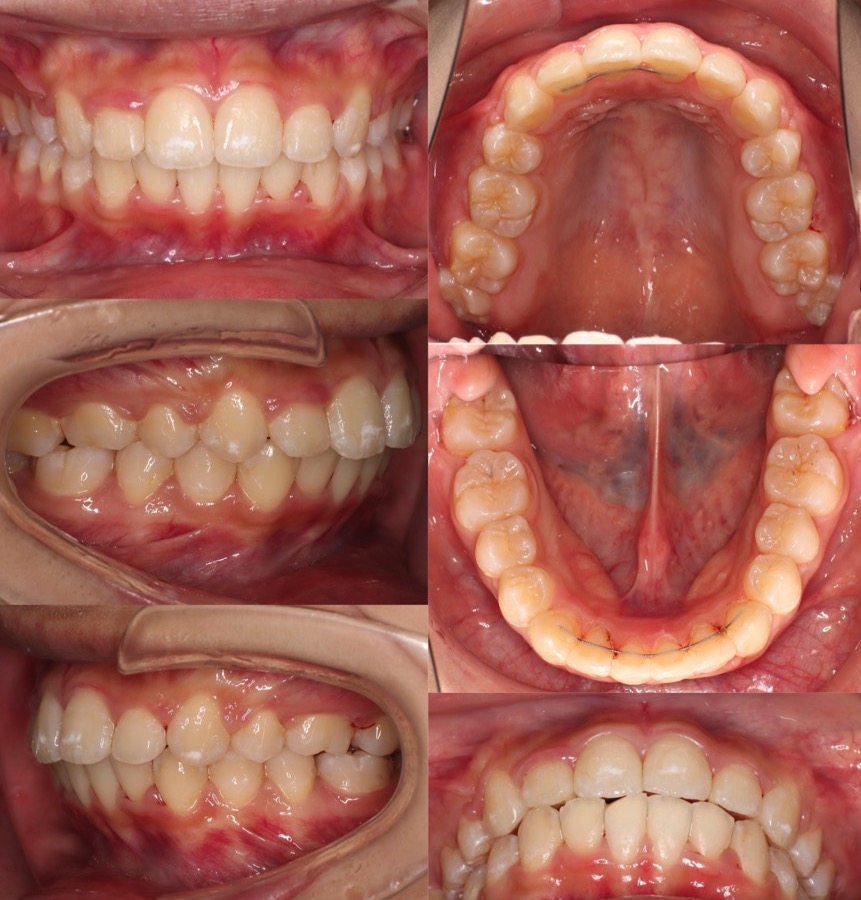

20代女性・マウスピース型矯正装置・上抜歯

<症例概要> 難易度★★★★★

主訴:出っ歯・ガタガタ

年齢・性別:20代女性

住まい:千葉県千葉市

症状:下顎後退・上下叢生

治療方針:抜歯空隙閉鎖

治療装置:マウスピース型矯正装置(アライナー装置)

抜歯:上左右第一小臼歯(計2本)

治療期間:2年11か月(1週間交換)

アライナー枚数:72+46+26ステージ

リテーナー:上下フィックスタイプ+クリアタイプ

治療費用:990,000(税込)

代表的副作用:痛み・治療後の後戻り・歯根吸収・歯髄壊死・歯肉退縮

▶︎その他の副作用

【治療シミュレーション】

上の抜歯したスペースに、突出している前歯を移動していきます。下の歯並びは後方に起こしながら並べていきます。

※マウスピース型カスタムメイド矯正歯科装置は完成物薬機法対象外の矯正装置であり、医薬品副作用被害救済制度の対象とはならない可能性があります。

重度の上顎前突でしたが、歯並びがV字型であったため、抜歯に加えて歯列形態の修正も利用して大きく前歯を引っ込めることに成功しました。下あごが小さいため、横顔の変化は微量となりましたが、限界に近かった思います。